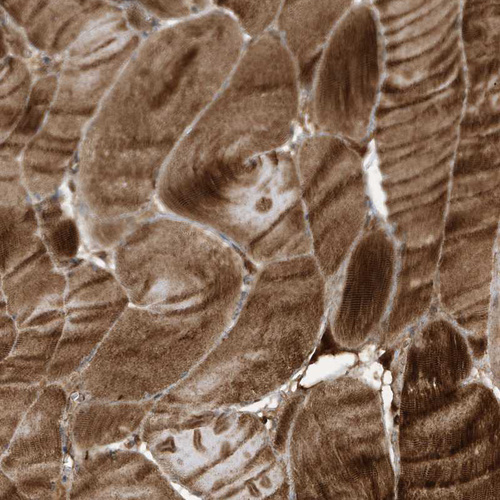

Immunohistochemical staining of human rectum shows strong cytoplasmic positivity in glandular cells.